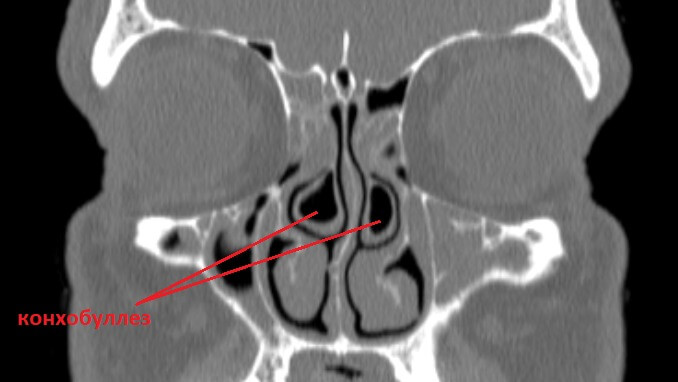

Буллезная гипертрофия носовых раковин (конхобуллез)

Носовые раковины (верхняя, средняя и нижняя) — это парные анатомические структуры носовой полости, отграничивающие носовые ходы и обеспечивающие большую площадь поверхности для согревания и увлажнения вдыхаемого воздуха. В некоторых случаях носовая раковина изначально представляет собой гипертрофированный (увеличенный) “пузырек” вместо плоской кости. Занимая большее пространство в носу, она постепенно приводит к изменению состояния околоносовых пазух и структур полости носа. Данное состояние называется конхобуллез. В Москве лечением гипертрофии носовых раковин занимается клиника ЛОР Центр.

Конхобуллез классифицируют по местоположению: гипертрофия верхней, средней или нижней раковины. Также существует система классификации по степени поражения, основанная на клиническом обследовании и компьютерной томографии.

Классификация по степени поражения:

- 1-я степень — 0-25% окклюзии (закрытия просвета);

- 2-я степень —26-50%;

- 3-я степень — 51-75%;

- 4-я степень — 76-100%.

Заболевание можно заподозрить при проведении эндоскопического обследования полости носа, но подтверждается с помощью компьютерной томографии носа и околоносовых пазух. На томограмме четко видны локализация и степень поражения.